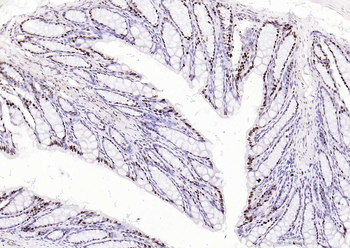

100 μl, 200 μl, 50 μlPhospho-SMAD5 (Ser463 + Ser465) Recombinant Rabbit Monoclonal Antibody [orb559123]

ICC, IF, IHC-Fr, IHC-P, WB

Mouse, Rat

Human, Mouse, Rat

Rabbit

Recombinant

Unconjugated

50 μl, 100 μlPhospho-Smad3 (Thr179) Rabbit Polyclonal Antibody [orb313112]